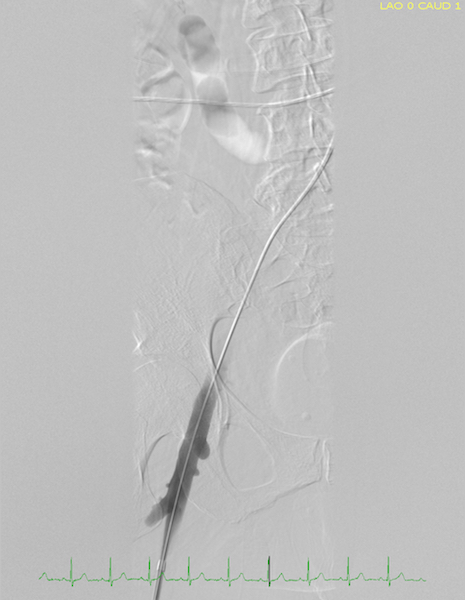

A thrombectomy and thrombolysis were performed on the left superficial femoral vein, the left common femoral vein, the left external iliac vein, and the left common iliac vein. Findings from venography of the inferior vena cava and iliac veins followed by intravenous ultrasonography confirmed compression of the left common iliac vein between the right common iliac artery and the spine, with resulting stenosis (Figure 2 and Video).

Figure 2. Image of venous flow during catheterization before stent placement.